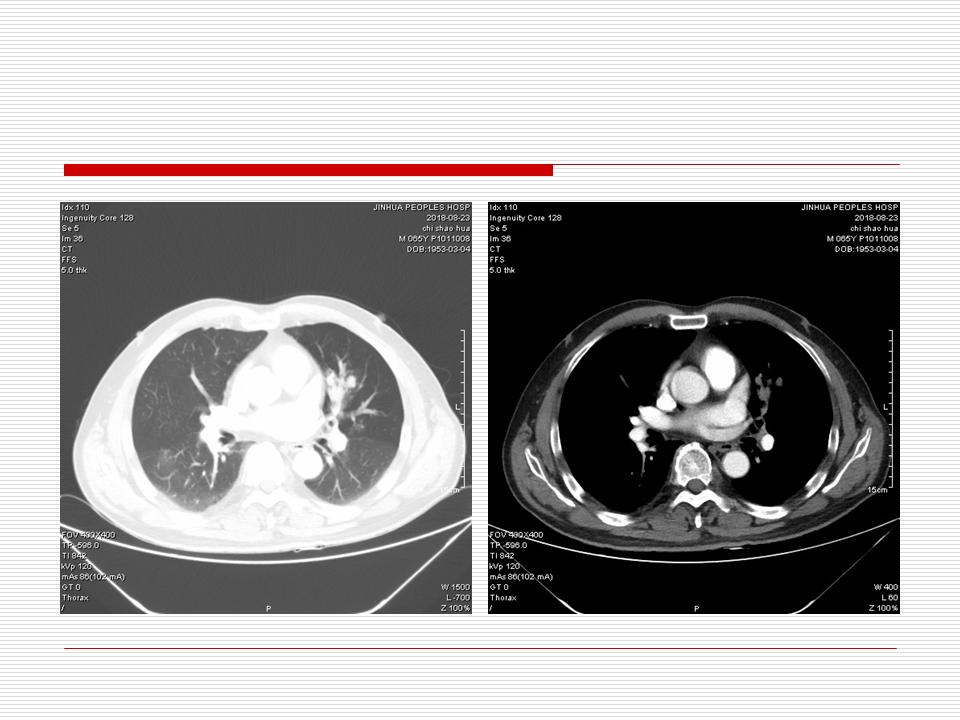

肺部阴影永恒且最重需要鉴别的是:到底是炎症还是肿瘤?但临床的病例中的影像表现难以界定或有些肿瘤特征,同时又有些炎症特点是非常常见的情况。作为临床医生我们怎么去总结分析,并找到之所以是炎症或之所以是肿瘤的细微差别或特点非常重要,也非常有用。2019.12.7浙江省2019年胸心外科学学术年会在宁波召开时,我的临床病例分析与经验总结<那些像肺癌的炎症与像炎症的肺癌>获得在大会交流的机会,以下为该PPT的内容,与你分享,希望对同道有益,有借鉴与启迪。若有探讨与进一不完善的建议,欢迎文末留言讨论: